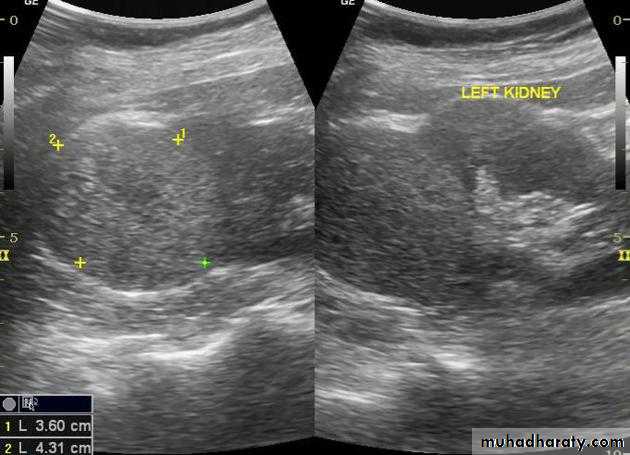

DX congenital PUJ obstruction.Renal masses

Almost all renal parenchymal masses are either simple cysts or malignant tumors(in adults RCC, in young children the commonest is Wilm’s tumor.Other causes of renal masses are benign masses like AML “Angiomyolipoma” , abscesses, hydatid and metastasis.

US can establish wheather a mass is a simple cyst (ignore it)or solid mass (mostly RCC)